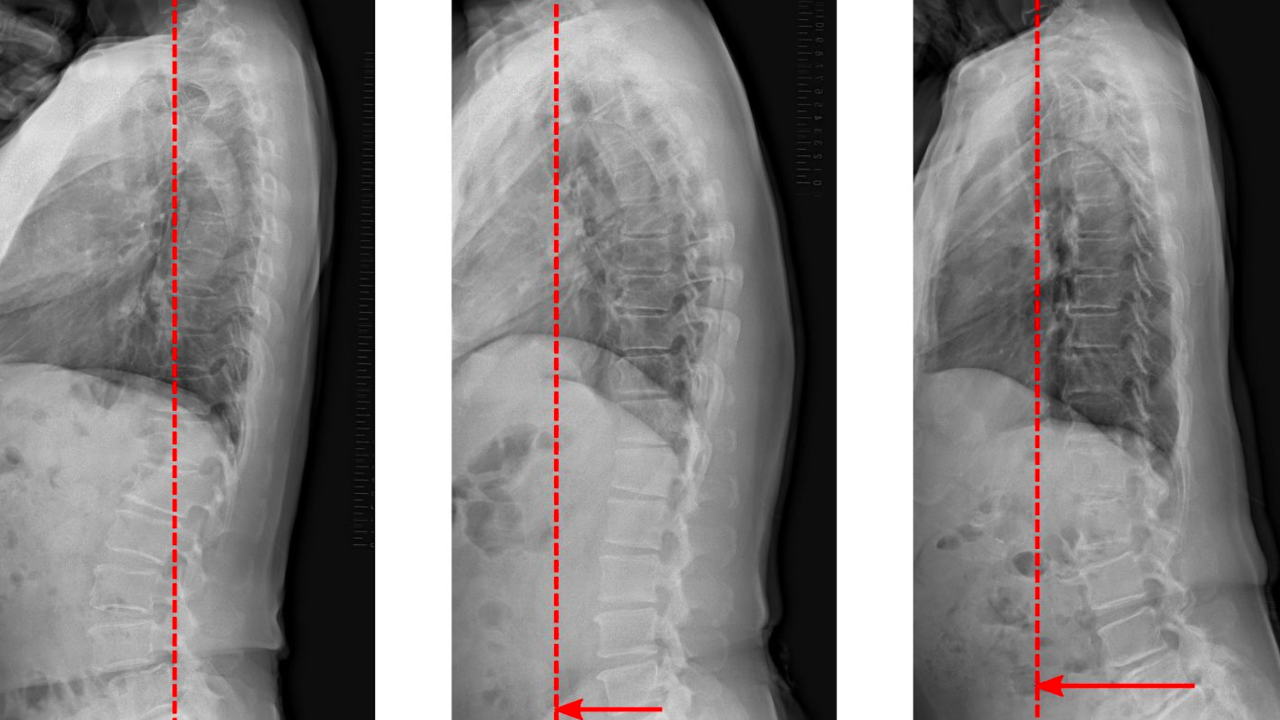

The scientists studied the data of Japanese people aged 50 to 89 years. It turned out that participants with a shift in the sagittal vertical axis (SVA) had an increased risk of mild cognitive impairment. The SVA is a straight line drawn from the C7 vertebral body perpendicular to the floor. It can progress with age.

Cognitive decline was observed at any age if the SVA deviation was greater than 70 mm in women. For men, a similar effect was observed with a deviation of more than 100 mm.